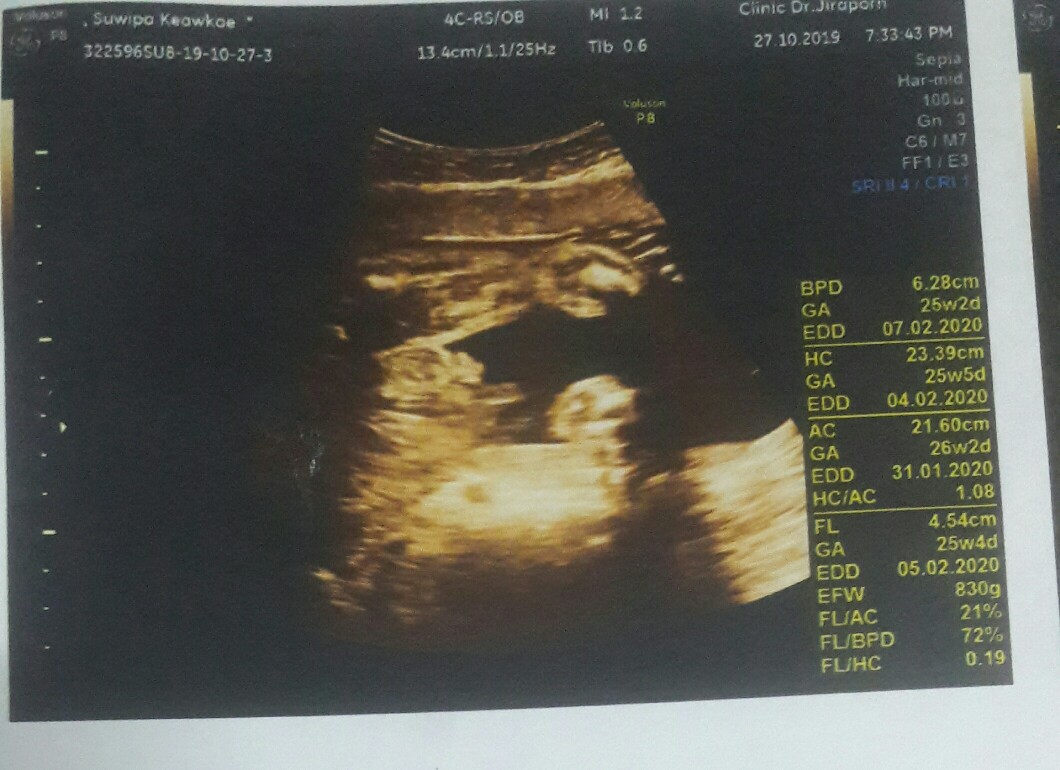

อัลตร้าซาวด์

แม่ๆคนไหนคลอดเดือนกุมภาพันธ์63บ้างคะ วันนี้ไปซาวด์มาหมอบอกว่าได้ลูกสาว ดีใจค่ะ แต่ดูใบซาวไม่ถนัดค่ะ